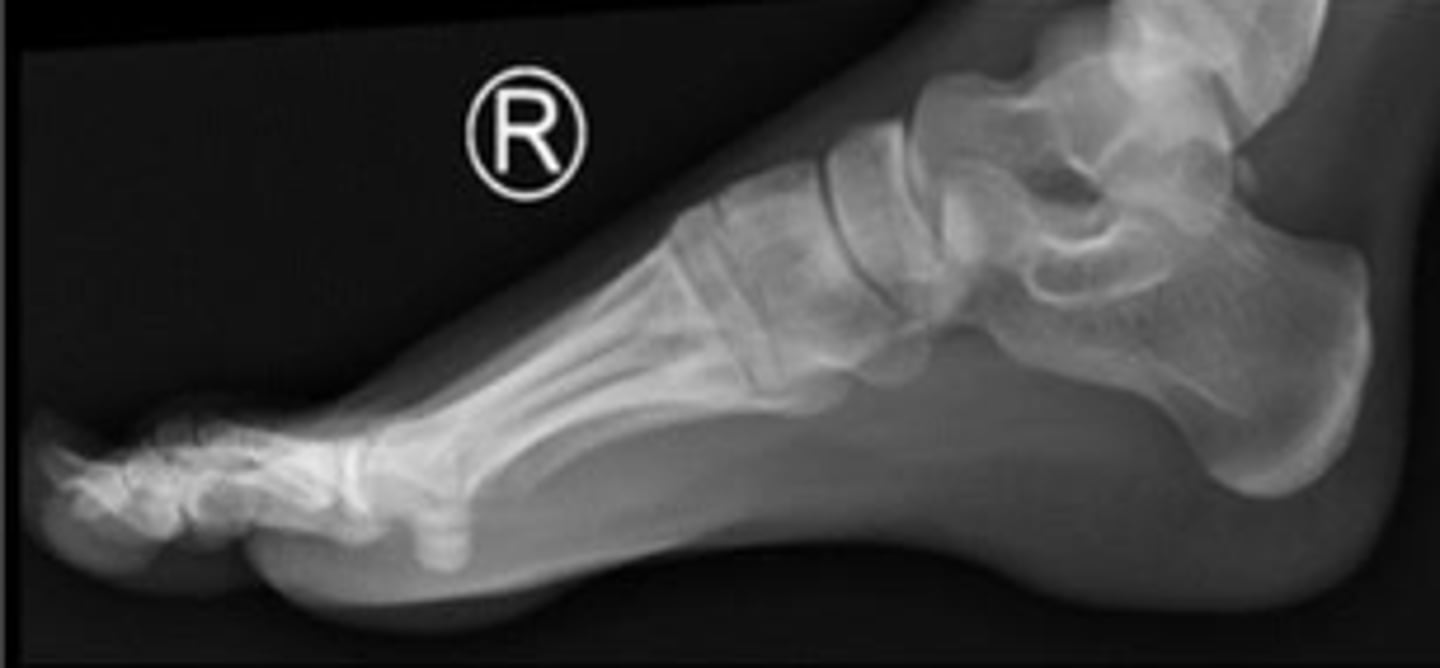

Right lateral foot

What is the name of the radiographic view?

Heel pad measurement

What is the name of the assessment?

Females: average 19mm (maximum of 23mm)

Males: average 19mm (maximum of 25mm)

What is the normal range for the assessment?

Achille's tendon thickness

4-8mm

Yes

Is the assessment within normal limits?

Overuse, ill-fitting shoes, tendinosis/tendinitis,

rheumatological diseases, etc.,

Name 2 conditions that may result in an increase in the measurement beyond the upper limit of normal ?

Head of the talus of the right foot

What are the arrows pointing to?

Calcaneus of the right foot